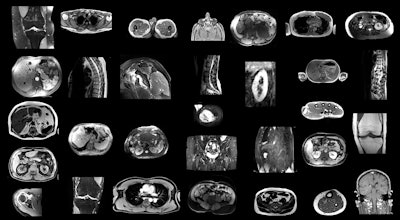

Example MRI scans in the training dataset. Since images were randomly sampled from clinical routine, the dataset contains a wide variety of different contrasts, pathologies, and image types. Images and caption courtesy of the RSNA.Example MRI scans in the training dataset. Since images were randomly sampled from clinical routine, the dataset contains a wide variety of different contrasts, pathologies, and image types. Images and caption courtesy of the RSNA.